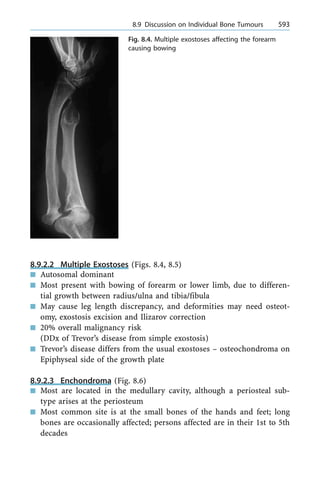

Tethered cord 374, 380

TFA 135, 137, 138

TFCC (term triangular fibrocartilage

complex) 244, 236, 248

± injury 245

±± chronic 247